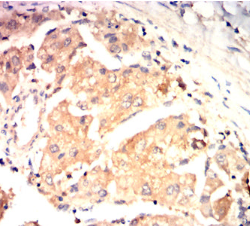

IHC    1/200 - 1/1000